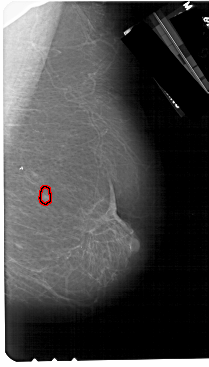

FILE: A_1267_1.RIGHT_MLO.OVERLAY

TOTAL_ABNORMALITIES 1

ABNORMALITY 1

LESION_TYPE MASS SHAPE OVAL MARGINS CIRCUMSCRIBED

ASSESSMENT 4

SUBTLETY 4

PATHOLOGY BENIGN

TOTAL_OUTLINES 1

BOUNDARY